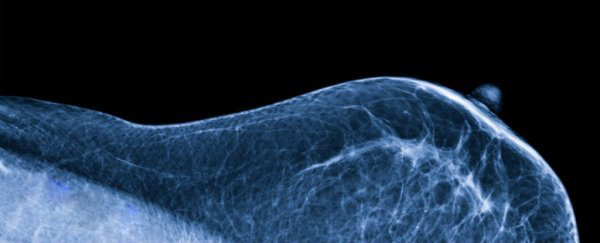

你可能没有意识到的是,女性的乳房组织中也住着微生物群,新研究已发现一个人的独特乳房微生物群能够预防或者提升这个人患乳腺癌的风险。

事实上,就在两年前,科学家们还认为乳腺组织完全不含有细菌。2014年的一项研究完全改变了这种看法。加拿大西安大略大学的科学家们表示乳房中其实含有丰富的细菌,这些细菌通过刺激附近的免疫细胞能够维持乳房组织的健康。

为了进一步调查,该团队做了一项新实验以便找出乳房组织中究竟存在哪种细菌,以及细菌是否会给女性患乳腺癌的风险带来影响。

他们分析了来自58名女性乳房组织中的细菌DNA,其中有13名参与者因长有良性肿瘤而做了乳房肿瘤切除术,45名女性因长有恶性肿瘤而做了手术。科学家们将这些样本与23名健康女性(从未被诊断出癌症)的进行对比。

他们发现在患有乳腺癌的女性乳房组织样本中,其细菌群含有较高比例的肠杆菌科、葡萄球菌和杆菌。在先前的研究中,科学家们曾发现这些细菌能够诱导人类希拉细胞DNA的双链断裂,而这种DNA损伤与癌症的出现有关。

另一方面,健康女性的乳房组织样本中,其细菌群则含有较高比例的乳球菌属和链球菌,它们有着较强的抗癌属性。比如嗜热链球菌,它产生的抗氧化剂能够中和一类会造成与癌症有关DNA损伤的活性氧分子。